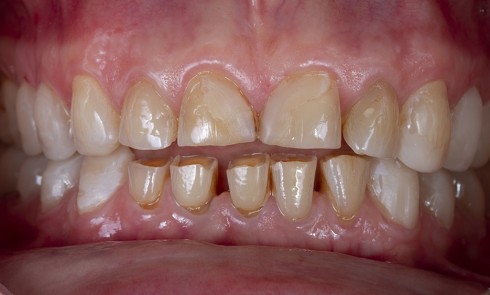

Article réservé à nos abonnés Matériaux et usures dentaires

La perte de tissus dentaires est fréquemment associée aux lésions carieuses. Or les bactéries ne sont pas toujours impliquées dans...

Article réservé à nos abonnés Les usures irrégulières : gérer la réalisation du mock-up

La sévérité des usures, comme leur étiologie (attrition, abrasion, érosion ou, plus fréquemment, une combinaison de ces dernières [1]), est...